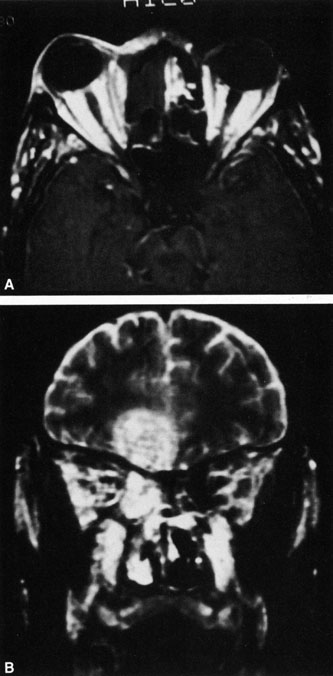

Fig. 23. Mucormycosis of the right ethmoidal sinus, with right orbital subperiosteal abscess formation. A. T1-weighted axial image. B. T2-weighted image. Note brain abscess.

CT shows sinusitis with or without bone destruction and is indistinguishable from other causes of orbital cellulitis.128 MRI may show carotid narrowing, occlusion, and absent flow in the superior ophthalmic vein (Fig. 24).72

Diagnosis is made by having a large index of suspicion and obtaining specimens of nasal turbinate, sinus, or infected orbital tissue. Large, branching nonseptate hyphae are readily apparent on hematoxylin and eosin staining or with methenamine silver staining (see Fig. 23). These hyphae can be grown on fungal culture.